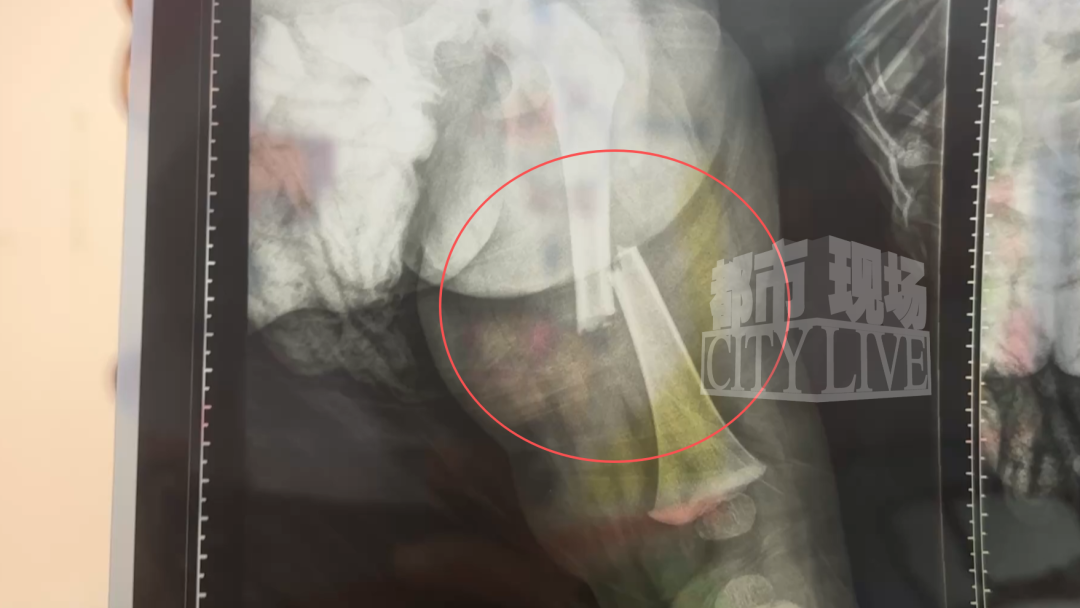

12月9日上午9点半,刘先生的岳母像往常一样,带着1岁多的孩子来到小区内的游乐设施处玩耍。谁也没想到,当孩子刚踏上顶部平台时,才往前走了两三步,脚下的木板突然发生脱落,来不及反应的老人没能拽住孩子,就这样孩子从3米多高的平台上坠落了下来。家属没敢耽搁,立刻将孩子送往南昌大学第一附属医院就诊,经过检查,孩子的伤情让全家人瞬间崩溃:左侧股骨骨折,断端分离错位。

更让家属揪心的是,由于孩子年仅1岁零5个月,身体无法承受全身麻醉,也就不能通过手术对骨折部位进行复位固定,只能采取保守的拉力牵引,在整个治疗过程中,孩子要全程忍受剧痛。“医生说成年人骨折都扛不住这份疼,更何况是这么小的孩子,每分钟都在哭,我们看着心里像刀割一样!”刘先生说起孩子治疗时的模样,声音满是无奈。更让他担忧的是,保守治疗若恢复不佳,孩子可能会留下长短腿。